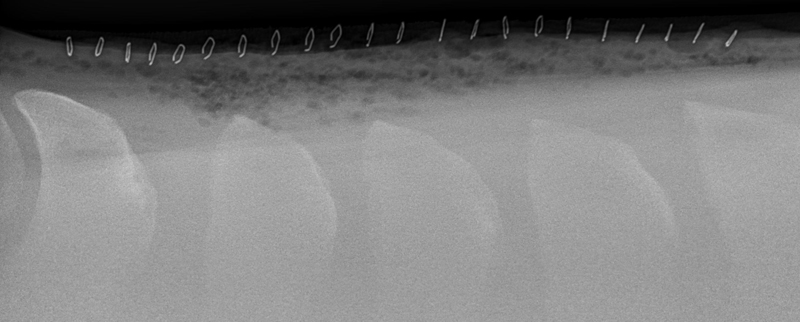

Kissing Spines, more scientifically known as impingement of the dorsal spinous processes, is a condition that has grown in relevance and impact throughout the last two decades with improved diagnostics and education. It’s hard not to feel a horse’s pain after taking just one look at an x-ray that indicates Kissing Spines. The condition can diminish athletic performance and render a horse unusable in severe cases, while other cases with the ugliest x-rays can experience no pain or performance implications. While still shrouded in some level of mystery, Kissing Spines is known to be conformational and most likely genetic. When spinous processes are conformationally close together they will inevitably contact, with that continual contact causing the modeling changes that are classically seen on radiographs.

Though Kissing Spines can be seen clearly in diagnostic imaging, truly understanding the nuances of the condition and how it can vary patient-to-patient is where things become less well-defined. Dr. Cliff Honnas, equine veterinarian, surgeon and founder of the widely respected Texas Equine Hospital in Bryan, Texas, is a sought-after authority figure in all things related to this condition, especially concerning its surgical treatment. “Kissing Spines is a condition where the dorsal spinous processes are too close together,” he explains simply. “These are the bones that make up the backbone of the horse directly underneath the saddle.” Normal horses should typically have a five millimeter or larger space between those bones, depending on the breed and size of the animal in question. In Kissing Spines cases, however, that space can be minimally to drastically narrowed until those bones are close together, touching or overriding.

While there are numerous conditions impacting the equine back, the diagnosis of Kissing Spines has increased fairly dramatically in recent years thanks to improved diagnostic techniques coupled with a greater focus on veterinary education. “Depending on who you choose to believe in the literature, Kissing Spines along with dorsal articular facet arthritis will account for 50 to 70 percent of orthopedic back problems,” says Dr. Kent Allen, sports medicine practitioner, founder of Virginia Equine Imaging, FEI Olympic-level veterinarian, current Vice President and Executive Director of ISELP and Chairman of the USEF (United States Equestrian Federation) Veterinary Committee. “The horse, which of course has a horizontal back as opposed to a human’s vertical back, doesn’t have disk problems like we do but rather has bony orthopedic problems that impact the way they bend, extend and jump, such as Kissing Spines and arthritis of the dorsal articular facets,” explains Dr. Allen. “In terms of Kissing Spines specifically, its location is most commonly from the base of the withers back to the thoracolumbar junction, from T16 back to L2-3. In contrast, arthritis of the articular area will often occur further back, about three inches forward to three inches behind the rear of an English Saddle.” While the general location and disease process have become more solidified, the clinical presentations exhibited by affected horses are wide-ranging and can create significant diagnostic and treatment challenges for veterinarians.

A condition where the dorsal spinous processes are too close together. Typically horses have about a five millimeter space between those bones; however, in Kissing Spines cases, that space is narrowed until those bones are close together, touching or overriding.

While the clinical signs of Kissing Spines can be ambiguous, Dr. Allen is quick to point out that not all horses with radiographic evidence of the condition display outward signs. “It's often a question of when this condition presents or if it presents. If we’re talking about a western pleasure horse or a horse that doesn’t ever jump over 2 feet 6 inches in its life, the animal may have Kissing Spines and never present. A look at the data on hundreds of horses with back pain revealed that the average age of presentation of back pain was about 6.5-years-old.”

While horses may be genetically predisposed to Kissing Spines and present clinical signs on an x-ray as early as 2-years-old, there are a great number of factors that go into determining if that horse will ever become clinical, including its level of training and specific discipline. Horses performing a sport that requires a high amount of flexing and bending of the back will oftentimes have increased odds of developing clinical symptoms of Kissing Spines in comparison to low-impact or more leisure-based sports — think of a cutting horse versus a horse primarily used on the trail. “A common situation is that we’ll see a horse come in for a pre-purchase exam, and since we’ll routinely do a back x-ray now, we’ll often see some degree of Kissing Spines,” says Dr. Honnas of a frequent and tough place that equine veterinarians find themselves in with potential buyers. “This could mean that space between those bones is reduced but very often not actually touching or overriding. We can also see horses that have tremendous Kissing Spines on an x-ray, but clinically are virtually normal and have no history of back pain. It makes it very difficult to decide on a pre-purchase exam what to recommend to the potential buyers in terms of their risk. This can be a top-end horse, doing its job well and with no disability. We’ll pick up Kissing Spines to some degree on the x-ray, and it’s impossible to state with certainty that horse’s risk of developing symptoms in the future.”

Following a thorough whole-body physical examination and a more specialized motion evaluation, the next step in a suspected case of Kissing Spines is to confirm the diagnosis with imaging. Drs. Honnas, Story, Williams and Allen are all significant proponents of the importance of those initial examinations prior to performing imaging. “I tell my clients, ‘I can x-ray your horse's back and look for things like Kissing Spines, but that could be just a tip of the iceberg,’ ” says Dr. Williams. “That comprehensive evaluation is absolutely necessary to form a complete picture.”

There are two primary diagnostic imaging methods that deliver the clearest picture — literally and figuratively — when dealing with a potential Kissing Spines case. “I teach combined imaging using x-ray and ultrasound to look at as much of the tissue as possible,” says Dr. Williams of his approach. While Kissing Spines can oftentimes appear clearly using x-ray alone, the use of this combined imaging approach delivers the most definitive diagnosis possible. “Ultrasound is the most sensitive tool to observe surface detail. It reflects off of bone. You can't see through it, but if the bone surface is uneven, it will tell you that. On an x-ray or a radiograph you can’t pick that up unless you get the perfect view,” says Dr. Williams of one reason he brings ultrasound into the equation. Another attribute of ultrasound is its ability to look at the supraspinous ligament, multifidus muscles and the facet joints, which are placed further down at the base of the spinous processes. “I talk about ultrasound surveys,” says Dr. Williams. “I don't just look with the ultrasound, then find something and walk away. I survey the back from the withers all the way back through the lumbar region. This gives me all of the information, and I can then better determine whether the horse has Kissing Spines alone, if the case is surgical and if there’s something else at play in addition to the Kissing Spines.”